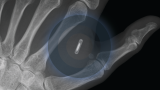

Tech2025のWebinarに出演したSjöblad氏によると、米粒ほどの大きさのマイクロチップは、人の皮膚の下、つまり腕の下か人差し指と親指の間に埋め込むことができるという。チップを埋め込んだ後、NFC対応デバイスを使って、ワクチンパスポートなどのデータを保存することができます。